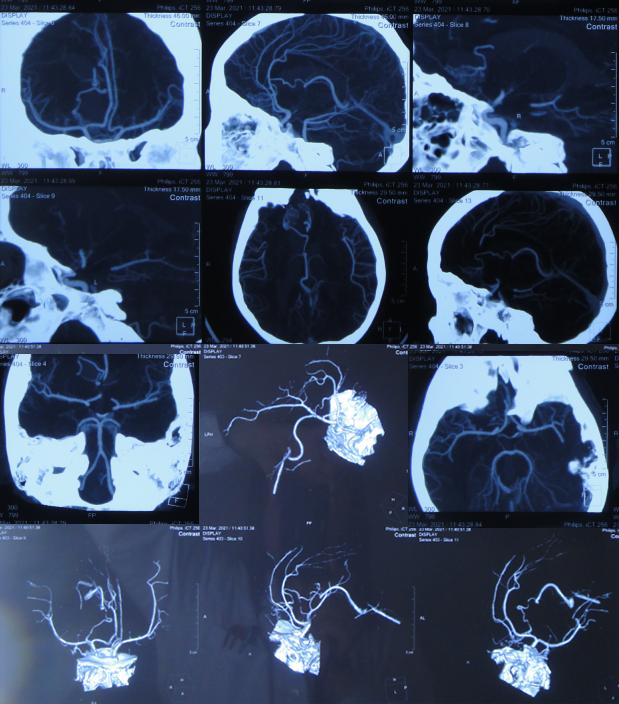

查脑CT后当天转至上级的江苏省徐州市某著名三甲医院,查脑血管造影( 图-2 )示未见明显异常,给予腰穿相关治疗;但当天出现发热,最高达37.7℃。

图-2: 2021年3月23日脑血管造影